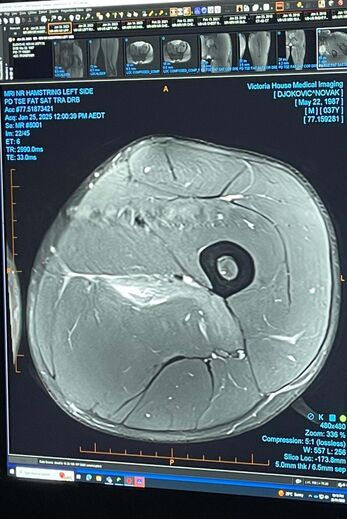

E foi por isso que este sábado o sérvio utilizou as redes sociais para publicar… uma prova de que a lesão sofrida é mesmo uma realidade.

"Pensei em deixar isto aqui para todos os especialistas de lesões desportivas que andam por aqui veram", disparou com ironia.